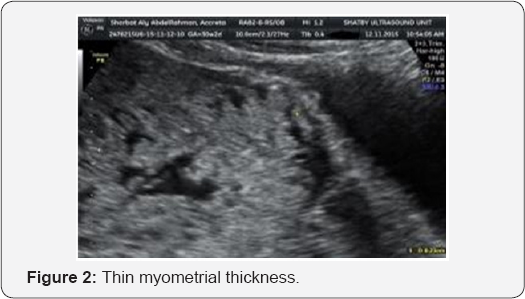

Myometrial thickness: retroplacental myometrium is thin as result of abnormal ingrowth of placenta. The smallest myometrial thickness in sagittal plane <1mm.

The lost retro placental space was statistically significant (p=0.033), with sensitivity 65%, specifity 74%, 70% accuracy, positive predictive value 67% and negative predictive value 72% . Of the included 45 cases, the myo metrial thickness measured by 2-D ultrasound ranged between 1mm and 15mm with a mean of 5.40±3.22.

Myo mertrial thickness was <5mm in 14 cases (31.1%), 5-10mm in 23 cases (51.1%) and >10mm in 8 cases (17.8%) of cases.

The myo metrial thickness was statistically significant (p=0.049). With sensitivity 86.7%, specificity 73.3% and 75.5% accuracy.

Finberg and Williams [13] found that number and bizarre appearance of lacunar spaces was directly correlated with certainty and severity of morbidly adherent placenta. In a recent systematic review, overall pooled sensitivity and specificity of lacunar spaces from 13 studies was 77% and 95% with an overall diagnostic accuracy of 0.884 [13]. When multiple, especially 4 or more lacunae, these findings have been correlated with a detection rate of 100% for placenta accreta. This marker also has low false-positive rates, but it should be noted that placenta accreta has been reported with absent multiple vascular lacunae. The myometrial thickness in our study has high predictive value. It was ranging between 1mm and 15mm with mean of 7.07±3.81for placenta accreta, 4.95±2.65 for placenta increta and 3.80±2.30 for placenta percreta. The sensitivity was 86.7%, specificity 73.3%, accuracy 75%, PPV 75% and NPV 80%. The cutoff point was 3.5, the myometrial thickness <3.5 indicate accreta.